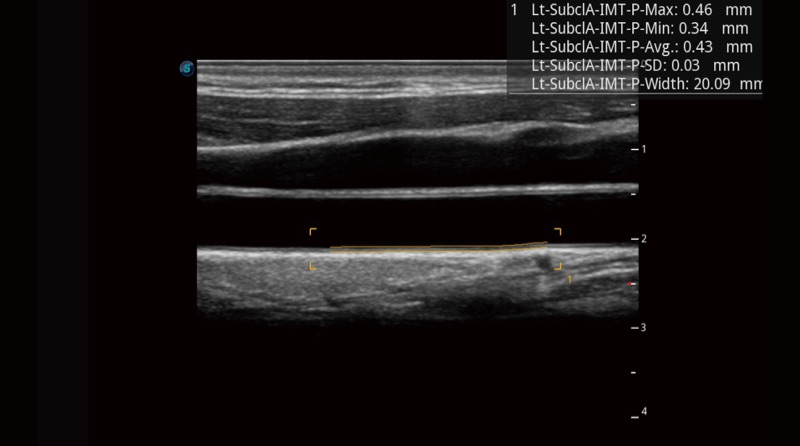

Mit Auto IMT wird die Messung der Dicke der vorderen und hinteren Intima-Media viel einfacher durch einfaches Platzieren des ROI.